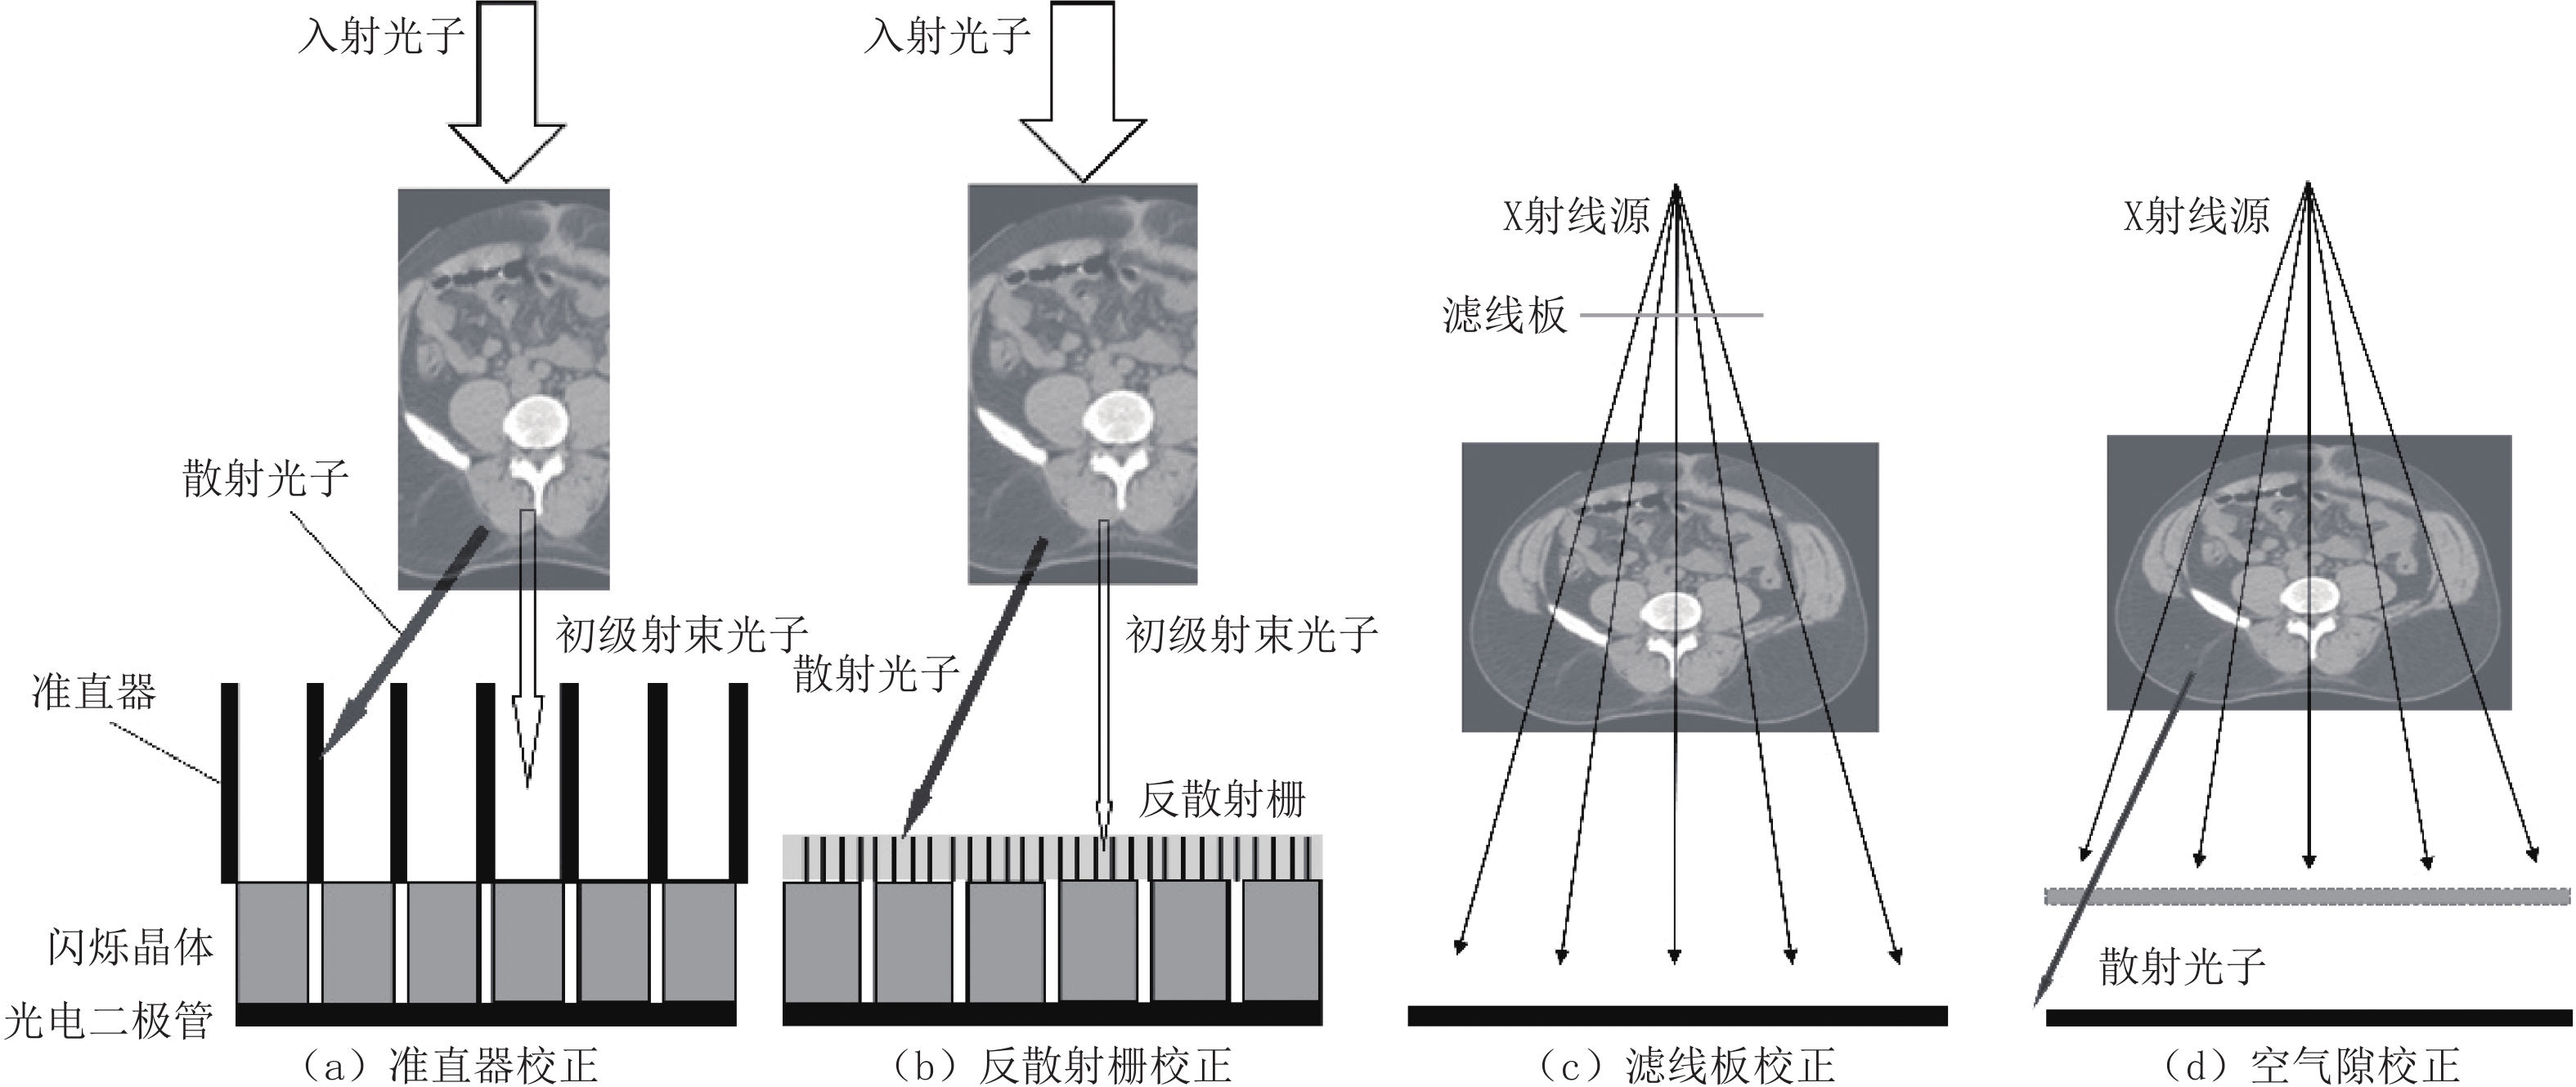

有研究证明深度学习校正结果优于散射核校正和混合校正的传统方法。在CT值准确性方面,深度学习网络方法较传统散射核估计方法和MC混合散射估计方法分别提高了75.5% 和27.7%[5-6],其可视化的校正效果如图4所示。